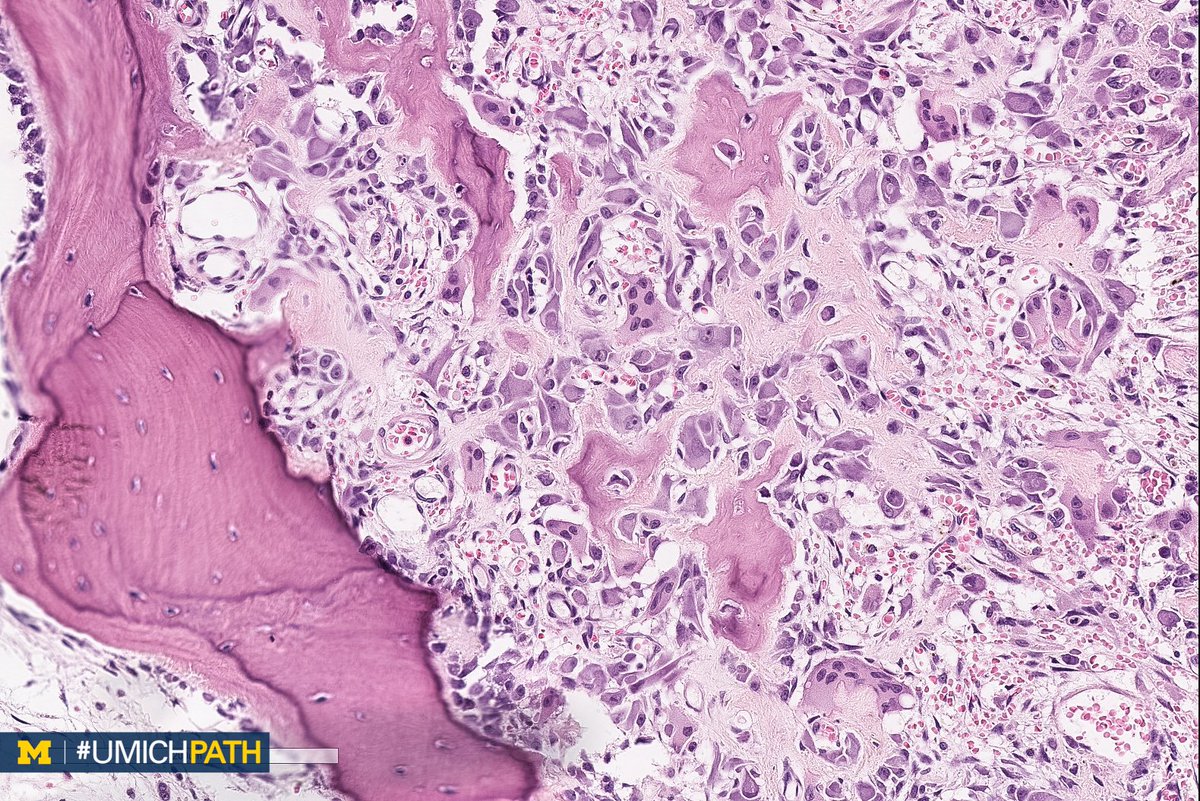

Osteoid Osteoma Histology Dental Pathology Osteoma osteomas are benign neoplasm often associated with facial. definition / general. definition / general. an osteoma is a benign bone lesion with no clear pathogenesis, almost exclusive to the craniofacial area. peripheral osteomas of the jaw bones are uncommon, and accordingly, patients with osteoma should be evaluated for. Benign, bone forming tumor composed of mature. Dental Pathology Osteoma.